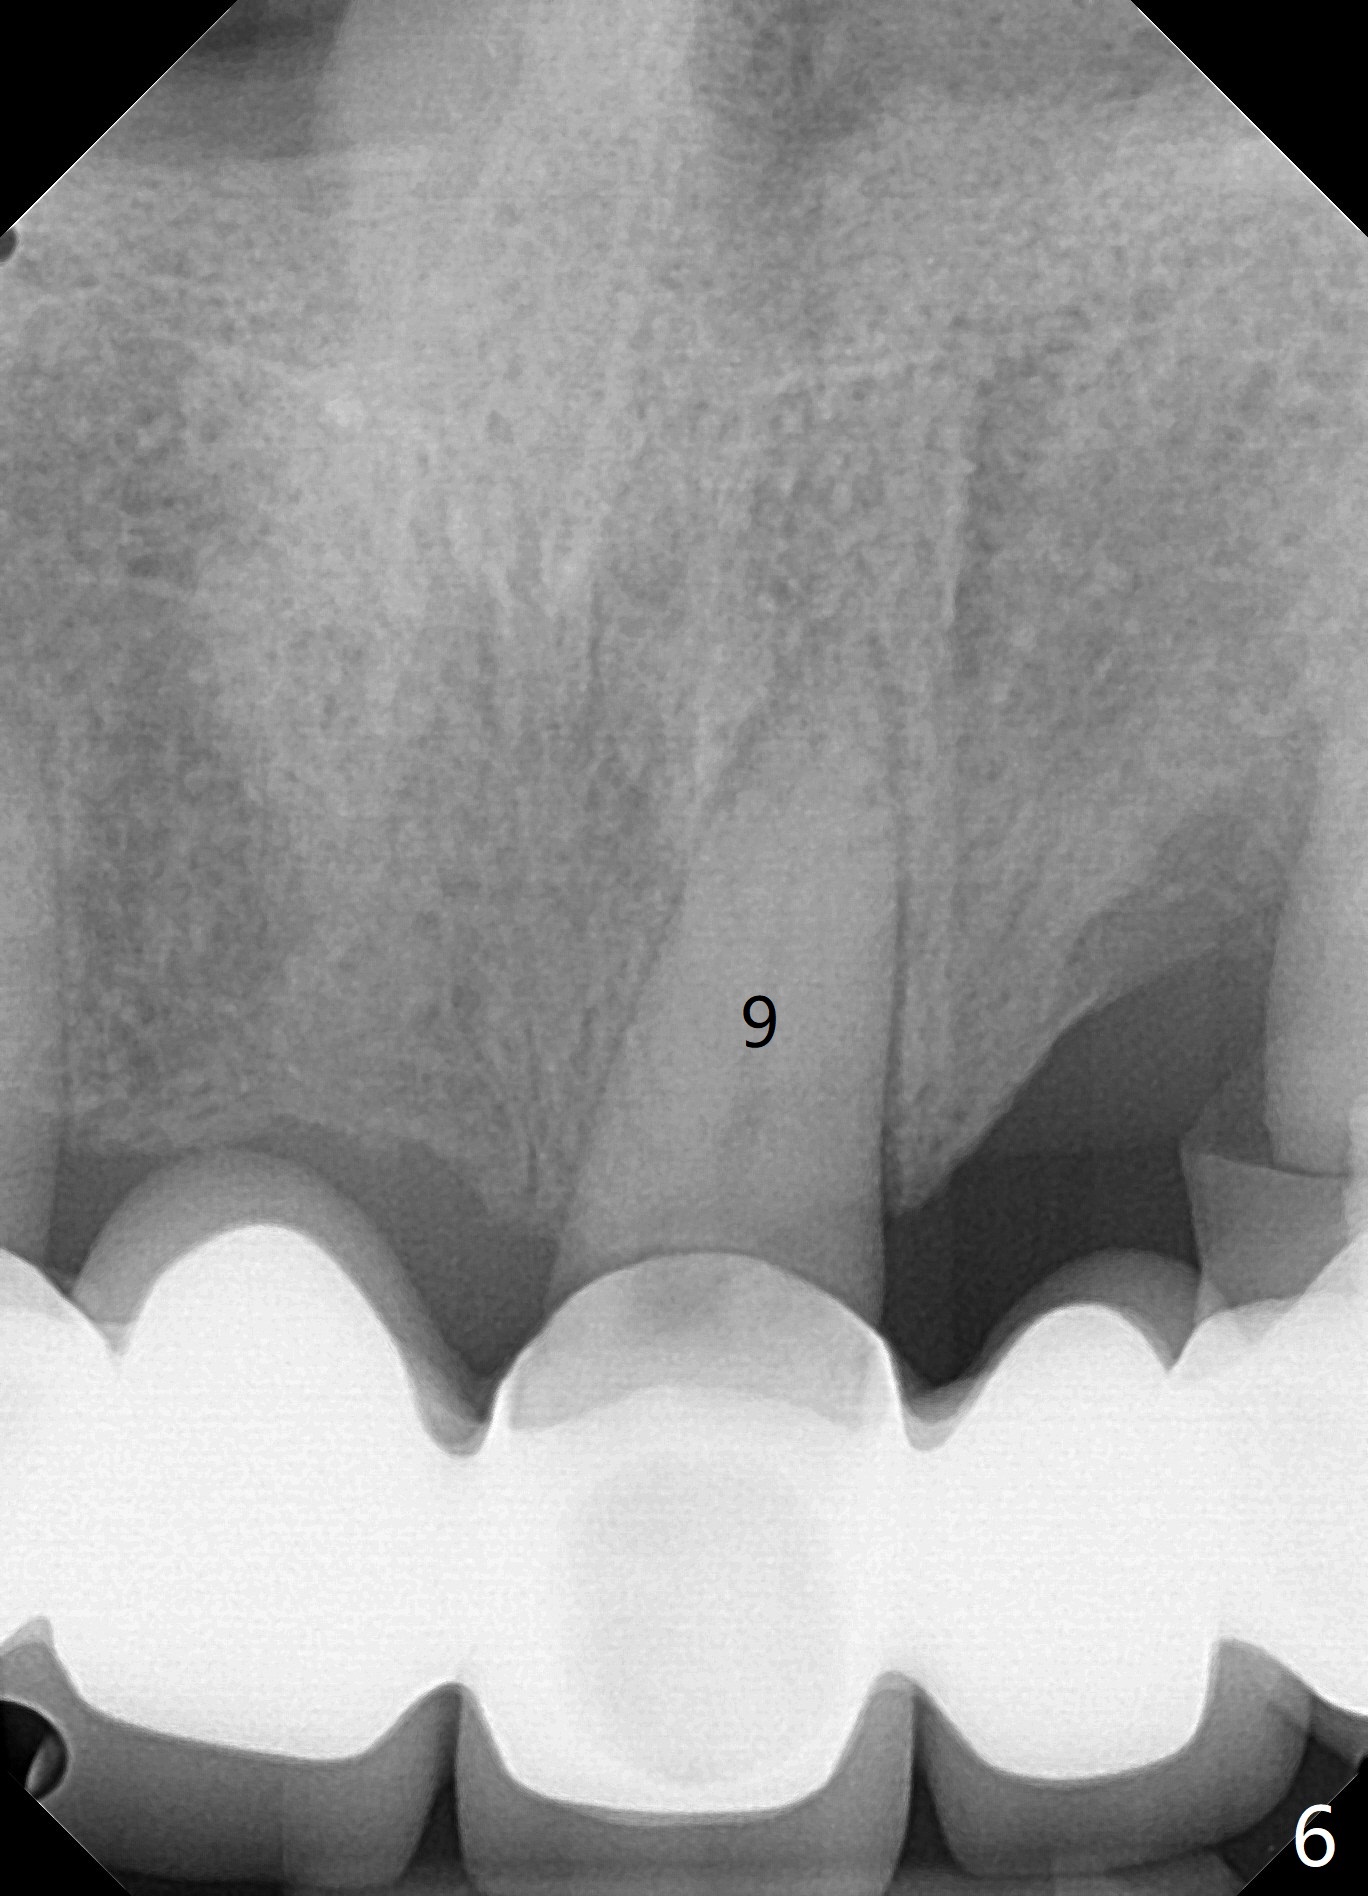

A 71 year old lady has issue with an upper bridge (#7-11, Fig.5-7). While one of the abutments (anchor teeth for FPD), #7, is "tender", the other (#11) fractures. Take Alginate impression (upper and lower) when she returns, pour models (no bubbles, 1 U, 2 L), and keep U Alginate for provisional. Section FPD at #7 and 9, take 12x9 cm CT with 2 cotton rolls and full arch impression for guide with bite registration. Prepare Endo Ice for #7 (tenderness). Tell the patient and her daughter that the lower left cantilever FPD is in bad shape, since the tooth #19 has large furca radiolucency (Fig.4 *). Next appointment should be scheduled for SRP (Fig.1-4).